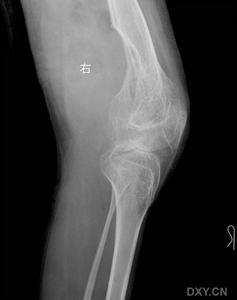

4.X線檢查

不同時期X線檢査可見骨質正常、骨質疏鬆、骨囊腫、關節破損等表現。